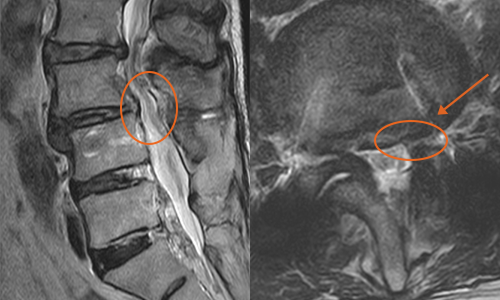

실제 척추 수술 사례

환자 : 65세 여성

증세 : 제 3,4번 요추간 돌출된 디스크와 비후된 황색 인대

경과 : 돌출된 디스크와 황색 인대가 제거된 결과, 비정상적인 신경의 신호가 하얗게 호전